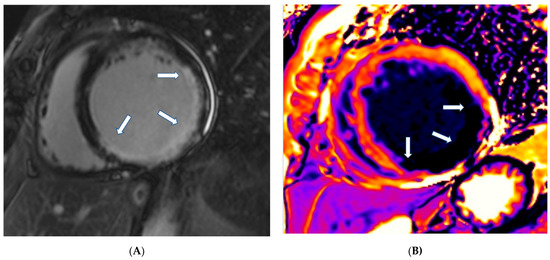

The presence of LGE in HCM, usually in the hypertrophic area, is a high-risk feature, and its presence should be used as a marker for major adverse outcomes such as sudden cardiac death (SCD), arrhythmias, and failure (HF) (Figure 4). It should be also included as an additional index in decision making for implantable cardioverter defibrillators for primary prevention [64]. LGE is usually present in segments with hypertrophy, in some end-stage cases, some segments may appear thinned with transmural fibrosis. The extent of LGE can be quantified either as a sum of the enhanced areas measured in grams or as a proportion of the total left ventricular mass (percentage of LGE). The percentage of fibrosis varies according to the quantification method used. From those methods, the only validated method against necropsy is the semi-automatic 2-standard-deviation technique, which consists of defining LGE as a 2-standard deviation above the mean signal intensity of the distant myocardium and constitutes the preferred quantification method. LGE is rarely observed in mutation carriers without LVH. In a study including patients with pathogenic sarcomere mutations and hypertrophic cardiomyopathy, subjects with mutations but no LV hypertrophy, and controls, CMR showed LGE in 71% of subjects with overt hypertrophy but in none of the mutation carriers without hypertrophy. Different studies have shown an increase in the risk of ventricular arrhythmias in patients with HCM related to the presence of fibrosis evaluated by LGE in comparison with individuals without LGE [63].

Figure 4.

Four chamber inversion recovery image showing severe hypertrophy and extensive LGE (arrows).

Finally, cardiac amyloidosis (CA) (Figure 5A,B), Takotsubo cardiomyopathy (TCM), non-compaction cardiomyopathy (LVNC), and cardiomyopathies associated with neuromuscular, metabolic, and autoimmune diseases are included in the unclassified cardiomyopathies.

Figure 5.

(A) Short axis LGE image showing diffuse amyloidosis (arrows). (B) Matching native T1 mapping of the same patient.